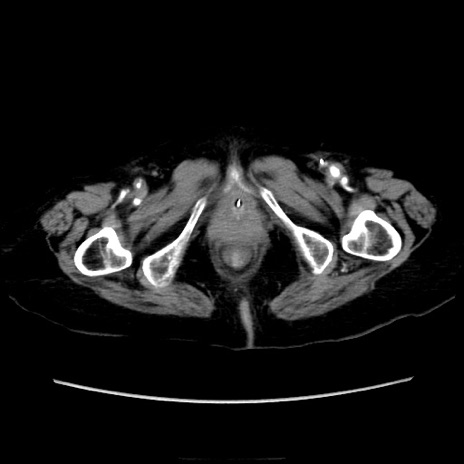

他院CT

横断像

冠状断像

矢状断像